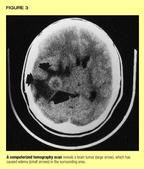

Signs and symptoms of brain tumors vary with the child's age and the location of the tumor. Sometimes symptoms are so vague that the pediatrician may think they reflect a common childhood illness, delaying the diagnosis. In other instances, findings may be so localized that the clinician can predict where the tumor is situated. Clinical manifestations may be caused by the tumor itself or by its secondary effects, which include peritumoral cerebral edema, hydrocephalus, increased intracranial pressure (ICP), or midline shifts caused by a combination of these effects (Figure 3). Clinical signs and symptoms depend on the tumor's location and size, and on whether it is obstructing the cerebrospinal fluid (CSF) pathway (Figure 4), which may lead to hydrocephalus and elevated ICP. In general, tumors that are growing aggressively are associated with severe symptoms, whereas initial signs and symptoms of slow-growing tumors are subtle.